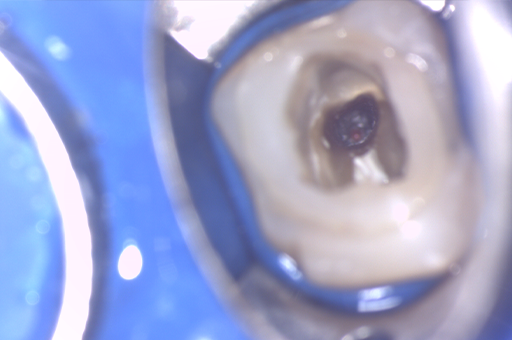

マイクロスコープによる治療

- 根の治療を開始して初めて認識する事実、歯根内部の穿孔、歯根の破折などが存在する場合、治療の成功率は低下いたしますが、できる限りの対応はさせていただきます。

- 治療中リーマー破折の可能性がございます。その場合には最大限対応しますが、除去できない場合もございます。